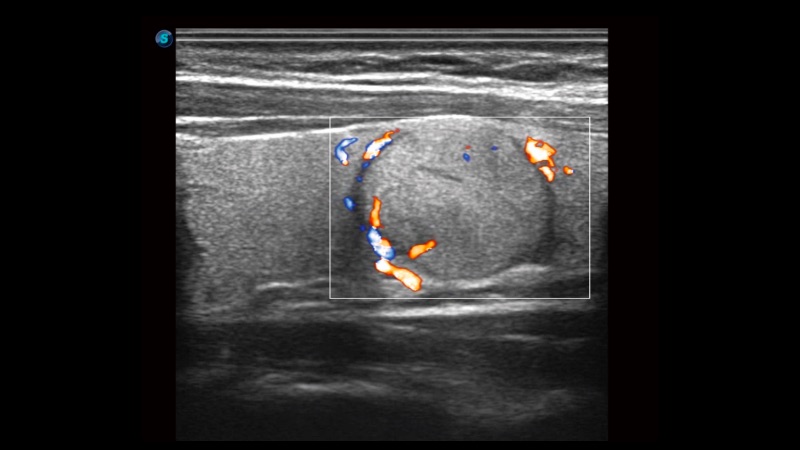

高分辨率血流成像技術(shù)提高了對低速血流信號的檢測能力。在提高空間分辨率的同時,也克服了血流外溢現(xiàn)象,為用戶提供更加真實的血流動力學(xué)信息。